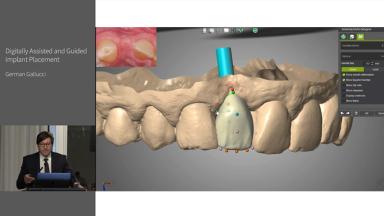

Digitally Assisted and Guided Implant Placement

This lecture presents the different types of digitally assisted and/or guided implant placement technologies, including Static Computer Assisted Implant Surgery (S-CAIS), Dynamic-Computer Assisted Implant Surgery (D-CAIS) and Robotic-Assisted Implant Surgery (RAIS). Dr. Gallucci explains how digital assistance not only facilitates virtual planning but may also elevate the treatment outcomes, offering improved design precision, increased reproducibility of treatment rendered, and a safeguard against failure or complications. Moreover, Dr. Gallucci also tackles the essential decision-making process regarding the use of digital guidance, distinguishing between its optional and essential roles in both standard and complex implant cases.

- identify the various types of digitally assisted implant technologies and their applications

- understand the benefits of digital planning and its impact on implant treatment outcomes

- assess the indications for using digital guidance in implant surgery to optimize clinical decision-making